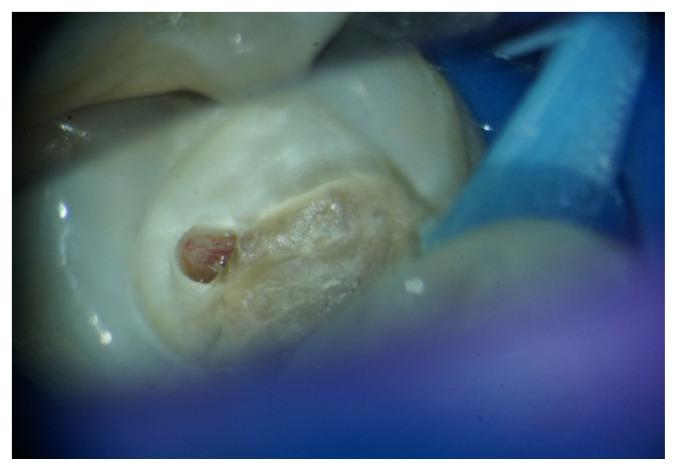

Magnification devices improve direct and indirect vision and precision being significantly higher in microscope use compared to the loupes. Dental loupes are the most commonly used devices for magnification, due to the more affordable prices and the ease of use without major changes in the working protocol and ergonomics. Loupes primary benefits reported refers to ergonomics and posture, restoration evaluation/detection and overall treatment quality. There are some disadvantages that limit the use of loupes among dentists: lack of fixed position (fine movements of the dentist's head disturb the image of the magnified operating field); the need to change the loupes to achieve different magnification. On the contrary, the use of a dental microscope require minimum adjustment and effort so as to reduce postural deviation while working. It has been more than 30 years since dental practitioners raised the issue of using dental operating microscopes (DOM) in restorative dentistry, identifying the benefits of magnification in diagnosis and treatment steps. The growth is evident in recent years, maybe because of the familiarity of dentists with dental microscopes which have already become implicit endowment for endodontic specialists. Fiber optic lighting is the key factor that complements the magnification offered by the microscope so that treatments can now be performed under increased safety conditions and in conditions of significantly higher quality than in the past. Since the beginning of the 2000s the principles of minimally invasive dentistry have been widely promoted in dentistry. These principles are major impetus for the use of microscope by dentists. Working with magnification leads dentists to be more conservative with dental tissues.